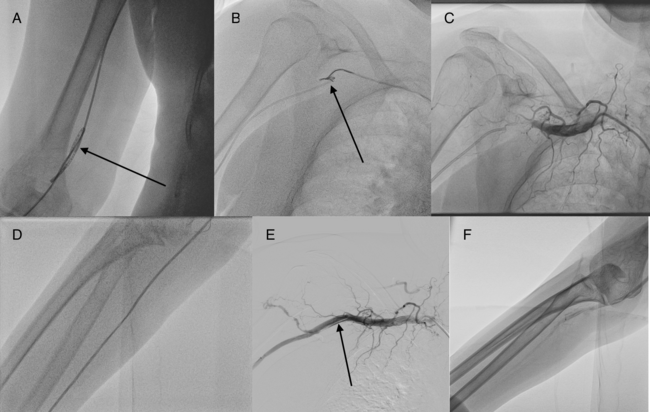

After the renal angiogram, there was a loss of arterial pressure tracing. Fluoroscopy revealed kinking and double knotting of the catheter at the level of elbow (Figure, A; Video 1) with severe spasm. All previously described techniques to open the loop, including rotating the catheter in the opposite direction, use of 0.035-inch guidewire and coronary 0.014-inch guidewire to cross the kink, and mother-and-child technique, failed. Use of a sphygmomanometer inflated above the kink to supra-systemic pressure also failed. Multiple attempts lasting a total of 120 minutes to snare the tip of the kinked catheter with a 6-Fr gooseneck snare (Lifetech) (Figure, B; Video 2) in a 6-Fr JR catheter from 7-Fr right femoral access failed due to aortic tortuosity allowing limited movement of the snare and severe radial spasm allowing minimal movement of the kinked catheter.

At this time, we contemplated subjecting the patient to surgical removal. A diagnostic angiogram showed thrombotic occlusion of the axillary artery (Figure, C; Video 3) due to repeated attempts to snare, despite activated clotting time being greater than 250 seconds. A glidewire (Terumo) was advanced across the occlusion and a peripheral 5 × 100-mm Ultraverse balloon (Becton Dickinson) was inflated for the vascular thrombosis. The inflated balloon fixed the catheter tip internally, and gentle pulling of the kinked catheter opened the loop (Figure, D; Video 4). Subsequently, a 0.035-inch guidewire (Terumo) was introduced and the kinked catheter was removed (Video 5). An angiogram showed axillary artery dissection (Figure, E; Video 6) with acceptable distal flow (Figure, F; Video 7), which was managed conservatively. The total procedure time was 240 minutes. Low molecular weight heparin was given for 48 hours, and the patient remained asymptomatic at discharge with no signs of limb ischemia.